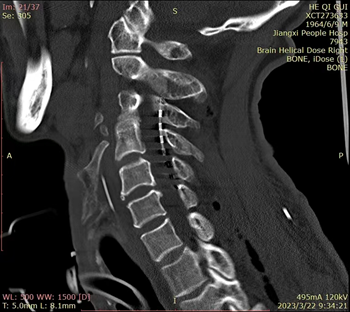

近日,中南大学湘雅医院江西医院(国家神经疾病区域医疗中心项目)神经外科收治一名颅脑外伤后昏迷不醒1月的患者何某,入院查体GCS评分8分,昏迷恢复量表(CRS-R)7分,有视物追踪,头颅CT提示弥漫性轴索损伤。经药物及床旁康复等治疗近1月,病情稳定,但仍昏迷不醒,结合病史、体征、影像学检查、长程脑电图、多次神经电生理评估,患者具备早期促醒条件,经家属同意后,于2023年3月21日在全麻下行“短时程脊髓电刺激(st-SCS)测试促醒治疗”,术中采用美敦力最新的脊髓电刺激Intellis刺激电极精确植入C2-4硬脊膜外腔,3月22日世界昏迷日开启体外刺激系统器。开机后第四天,患者从术前微意识状态改善至可遵嘱做动作,术后一周,患者意识完全清醒,自主动作。术后神经电生理监测显示相关传导通路完整性,长程脑电图产生积极的脑电变化。

图片一:术中照片及术后CT显示电极植入到位